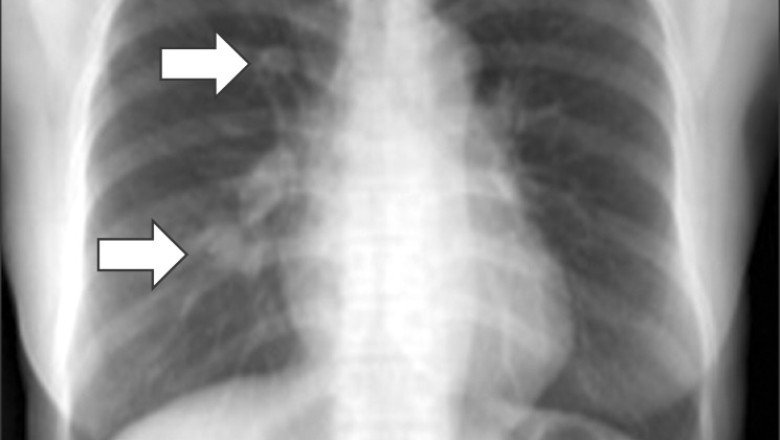

Diagnosis of Desmoid Tumors can be challenging, as they often do not have specific symptoms or signs. They can be detected incidentally on imaging studies such as CT scans, MRIs, or ultrasound. Biopsy is often necessary to confirm the diagnosis and rule out other types of tumors.